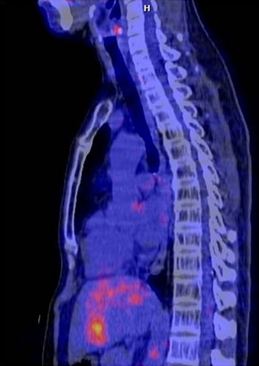

Kết quả chụp PET/CT kiểm tra cho thấy:  hình ảnh PET/CT cho thấy khối u tan hoàn toàn.

Trước điều trị

Sau điều trị (khối u tan hoàn toàn)